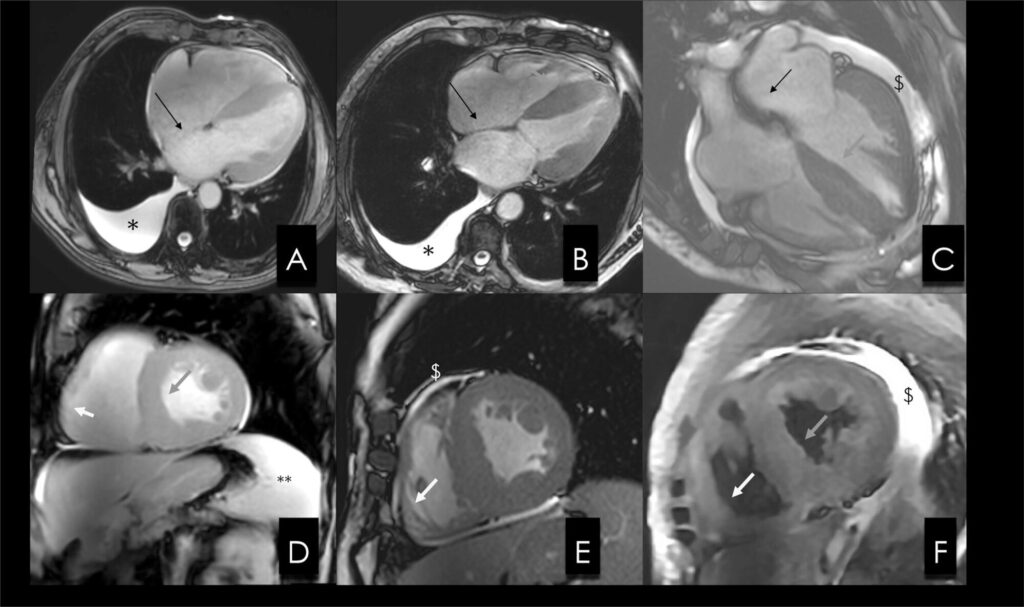

A real incidência de amiloidose cardíaca (AC) ainda é desconhecida e, ao menos em parte, isso se deve às dificuldades para confirmar o diagnóstico. Atualmente, porém, os diferentes exames de imagem e de genética podem, em associação com a apresentação clínica, confirmar o diagnóstico. A ressonância magnética cardíaca (RMC) pode contribuir para a confirmação diagnóstica e, mais recentemente, para o rastreio de familiares de portadores das formas hereditárias de AC.1 , 2 Neste artigo iremos rever as contribuições da RMC diante da suspeita ou do rastreio de AC, iniciando por rever as informações que o exame oferece e, em seguida, discutindo os cenários clínicos nos quais a RMC pode ser mais útil.